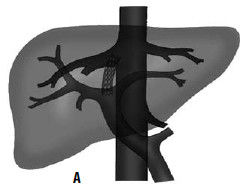

Рис. 84. Схема и рентгенограмма перитонеовенозного шунта при асците